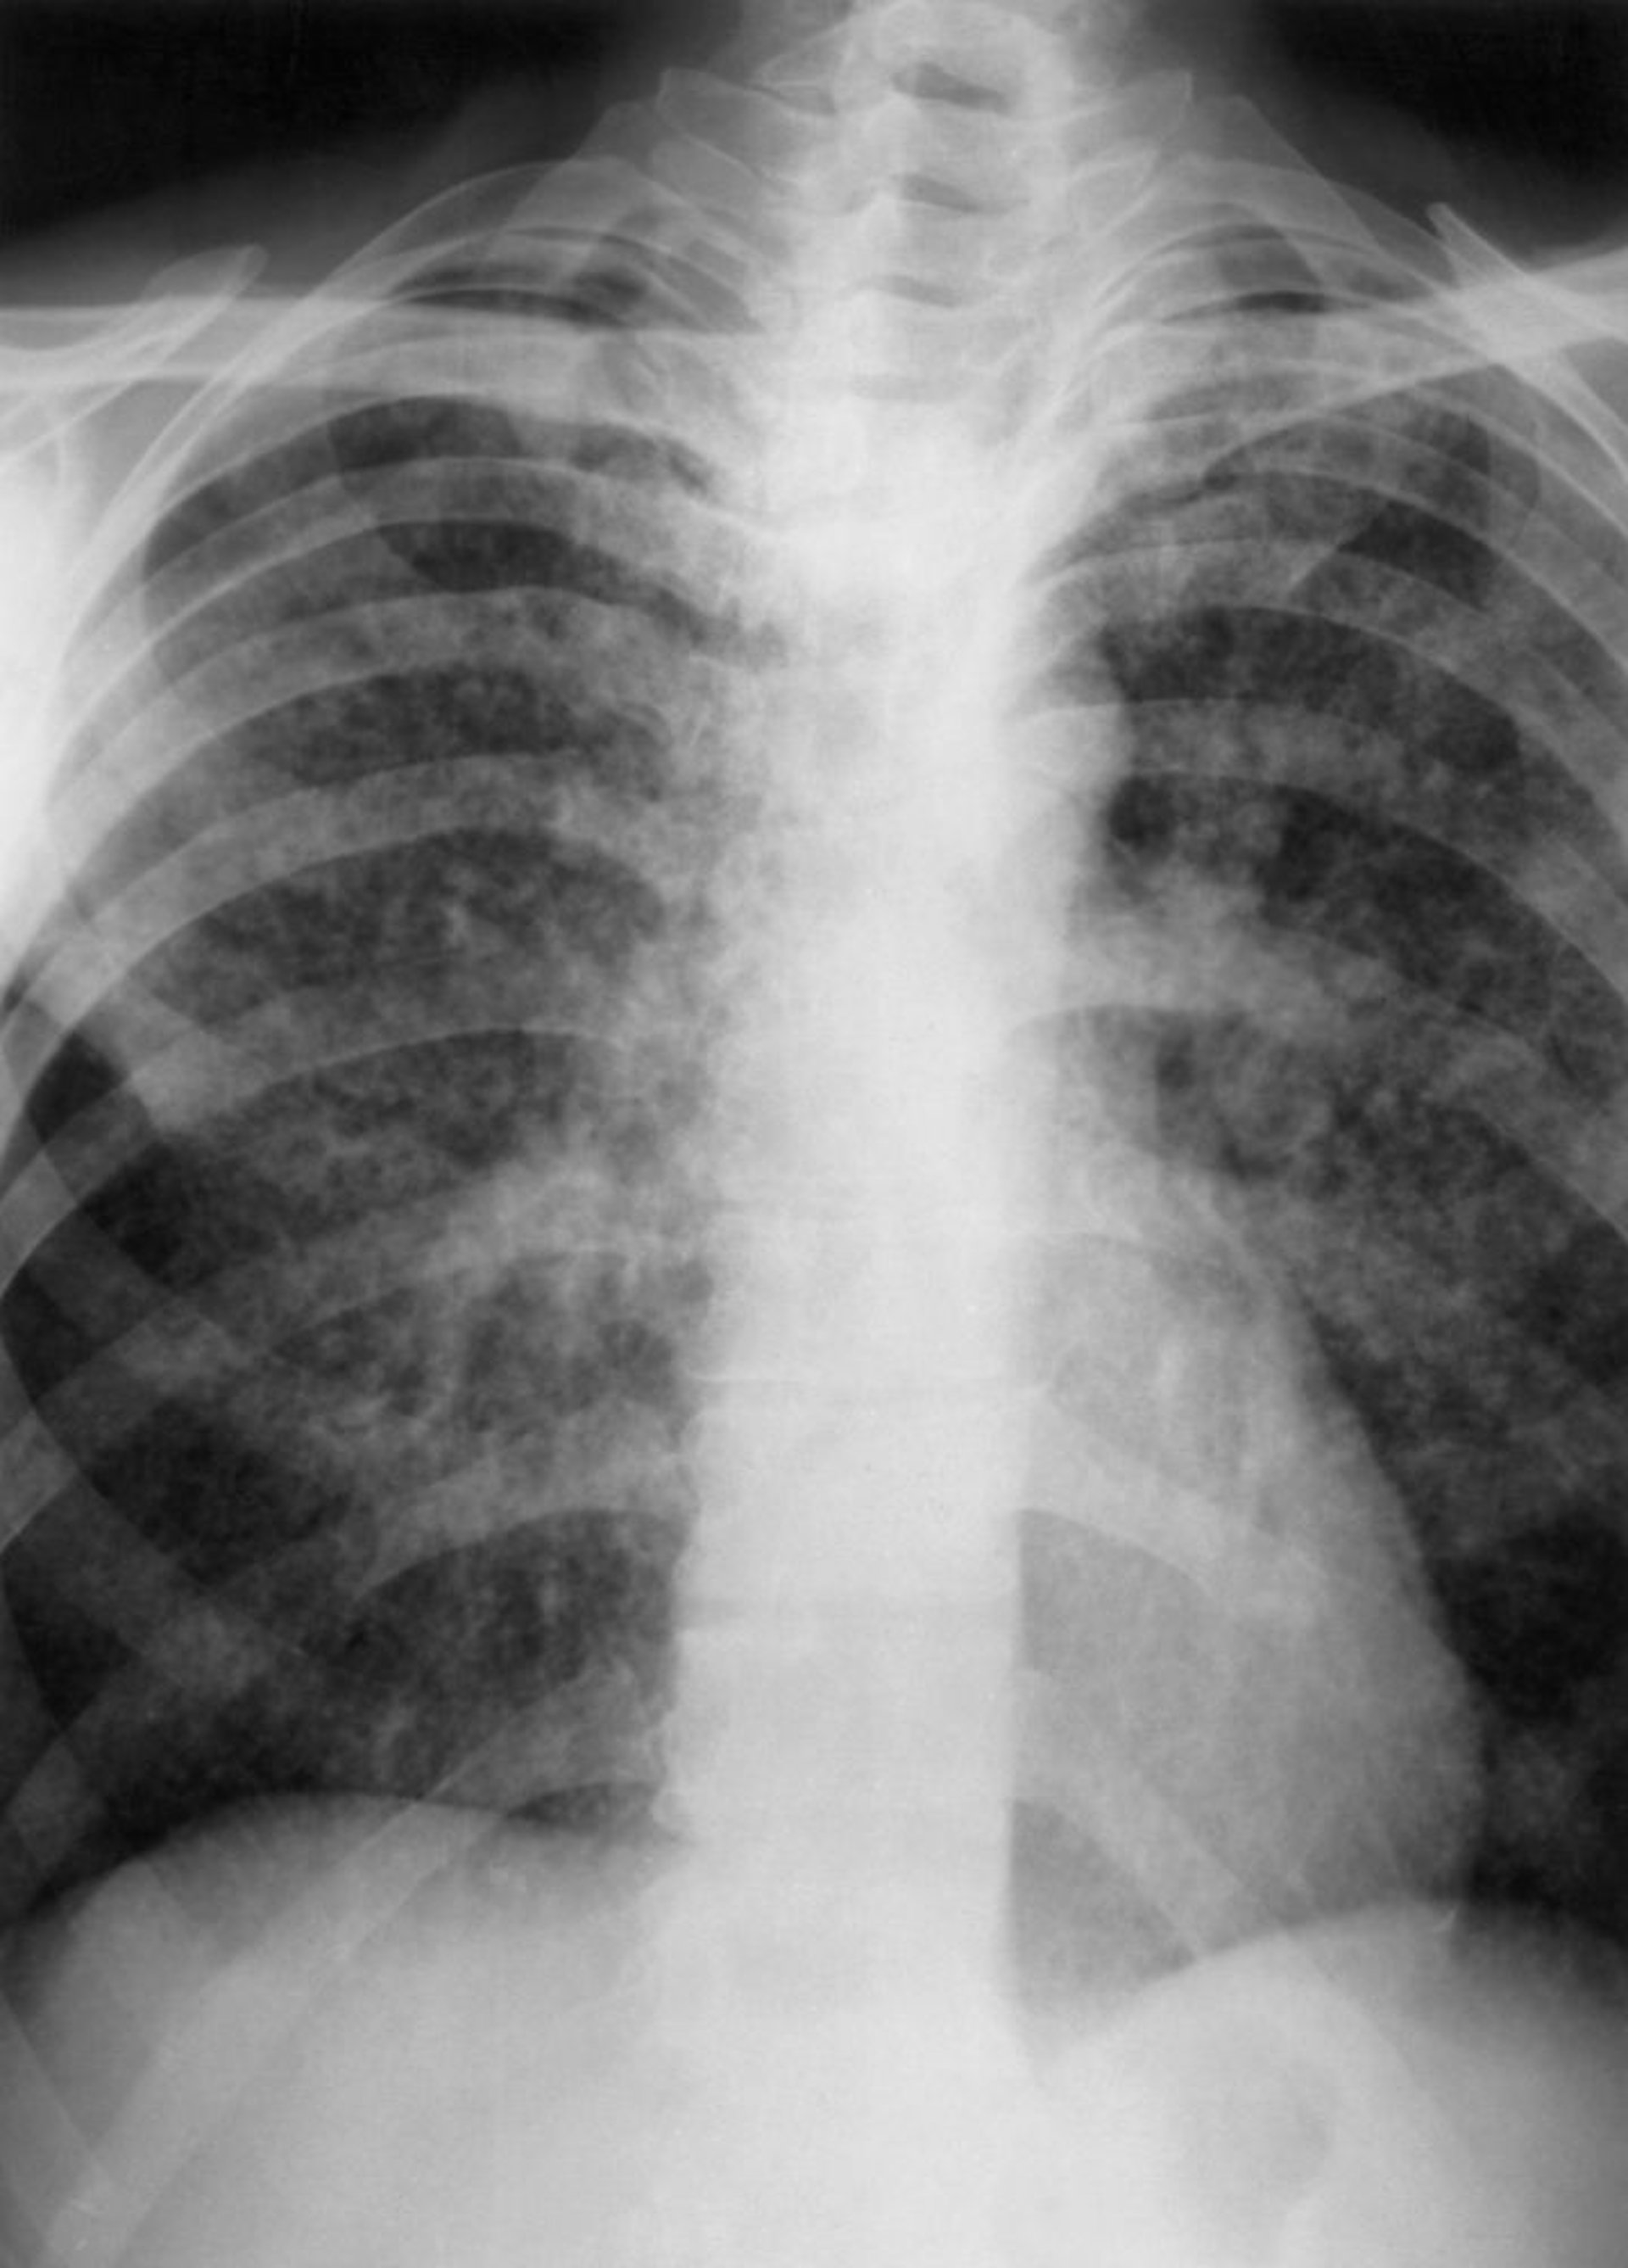

Tuberculosis miliar

Esta radiografía de tórax muestra hallazgos que sugieren tuberculosis miliar, incluidos nódulos intersticiales diminutos (p. ej., de 2 a 3 mm) distribuidos en ambos pulmones.